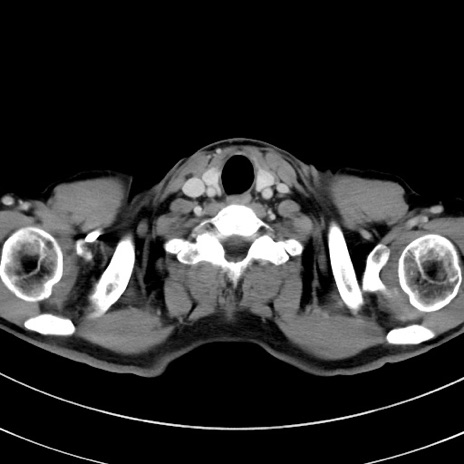

症例8(横断像)

【症例】 60歳代男性

【主訴】 黒色吐物

【現病歴】 4日前から嘔気自覚、2日前の朝食後にも嘔気あり、自分で手で嘔吐反射起こし嘔吐したところ血が混ざっていたため受診。

【既往歴】 5年前汎発性腹膜炎を伴う急性虫垂炎で手術、高血圧、前立腺肥大症、高脂血症

【身体所見】 腹部正中に手術癩痕あり 腹部平坦・軟圧痛なし膨満感あり

【データ】WBC 8400、CRP 4.54